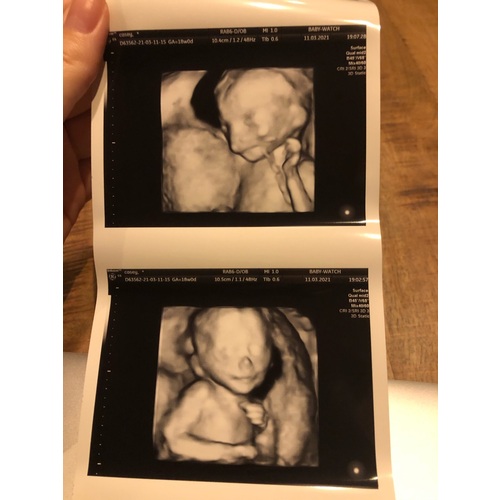

Pret Echo Rotterdam: De echo in Rotterdam met 4D technologie

Vierdimensionale echografie wordt in Rotterdam gebruikt als geavanceerde techniek om gedetailleerde beelden van de foetus te maken. Door middel van deze vernieuwende aanpak kunnen artsen een uitgebreider inzicht krijgen in de gezondheid en ontwikkeling van de baby. Door middel van deze technologie kunnen mogelijke complicaties vroegtijdig worden opgespoord en behandeld, wat de algehele gezondheid van zowel de moeder als het kind ten goede komt. .

In Rotterdam zijn diverse geavanceerde opties beschikbaar voor echografie, zoals 3D- en 4D-echo's die een gedetailleerd beeld van de foetus geven. Deze innovatieve echo-technologieën bieden een unieke kijk op de ontwikkeling van het ongeboren kind en kunnen ouders helpen zich nog meer verbonden te voelen met hun baby. Door gebruik te maken van deze geavanceerde echo-opties kunnen medische specialisten eventuele afwijkingen in een vroeg stadium detecteren en de juiste zorg bieden. Het is van belang om te weten dat deze echo's veilig zijn en geen schadelijke effecten hebben op zowel de gezondheid van de moeder als die van de baby.